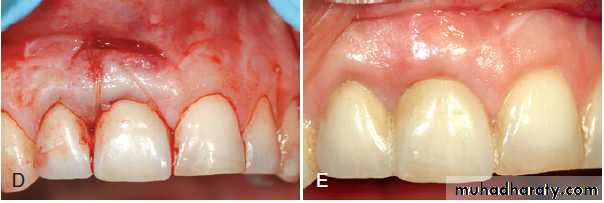

Guided tissue regeneration technique for root coverage. (A) Marked recession of the left maxillary cuspid. (B) Vertical incisions are made, and the membrane is placed over the recession. (C) Flap is sutured over the membrane. (D) Postoperative result, showing complete coverage of recession.